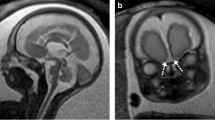

On the other hand, MRI is not hampered by maternal body habitus, oligohydramnios or fetal presentation, although it is frequently associated with maternal anxiety in advanced gestational age. It is not operator dependent, in contrast to ultrasound, which is affected by the sonographer’s technical skills. MRI has higher contrast resolution than ultrasound and provides supra- and infratentorial brain measurements [2]. Additionally, it shows superiority in identifying hemorrhage, ischemia or small cavitary lesions, while it maps the involvement of adjacent structures [6]. It easily produces images on three planes, which are better appreciated by clinicians and parents, showing superiority in revealing anomalies or structures that require sagittal views [6]. Certain skull base structures, such as the olfactory bulbs, the pituitary stalk and gland, and the semicircular canals (Fig. 1), are appreciable on MRI, which alters the characterization of specific anomalies [2].

Normal fetal brain structures seen clearly on MRI but poorly — or not at all — on US. a, b Coronal T2-weighted MR slices at 30 weeks of gestation show normal olfactory bulbs (a, arrows) and optic chiasm (b, arrow). c A midsagittal T1-weighted MR slice at 33 weeks of gestation marks the pituitary gland as an area of diffusely increased signal intensity corresponding to neuro- and adenohypophysis (arrow). d An axial T2-weighted MR slice at the level of the petrous bone at 32 weeks of gestation illustrates normal configuration of semicircular canals (arrows)